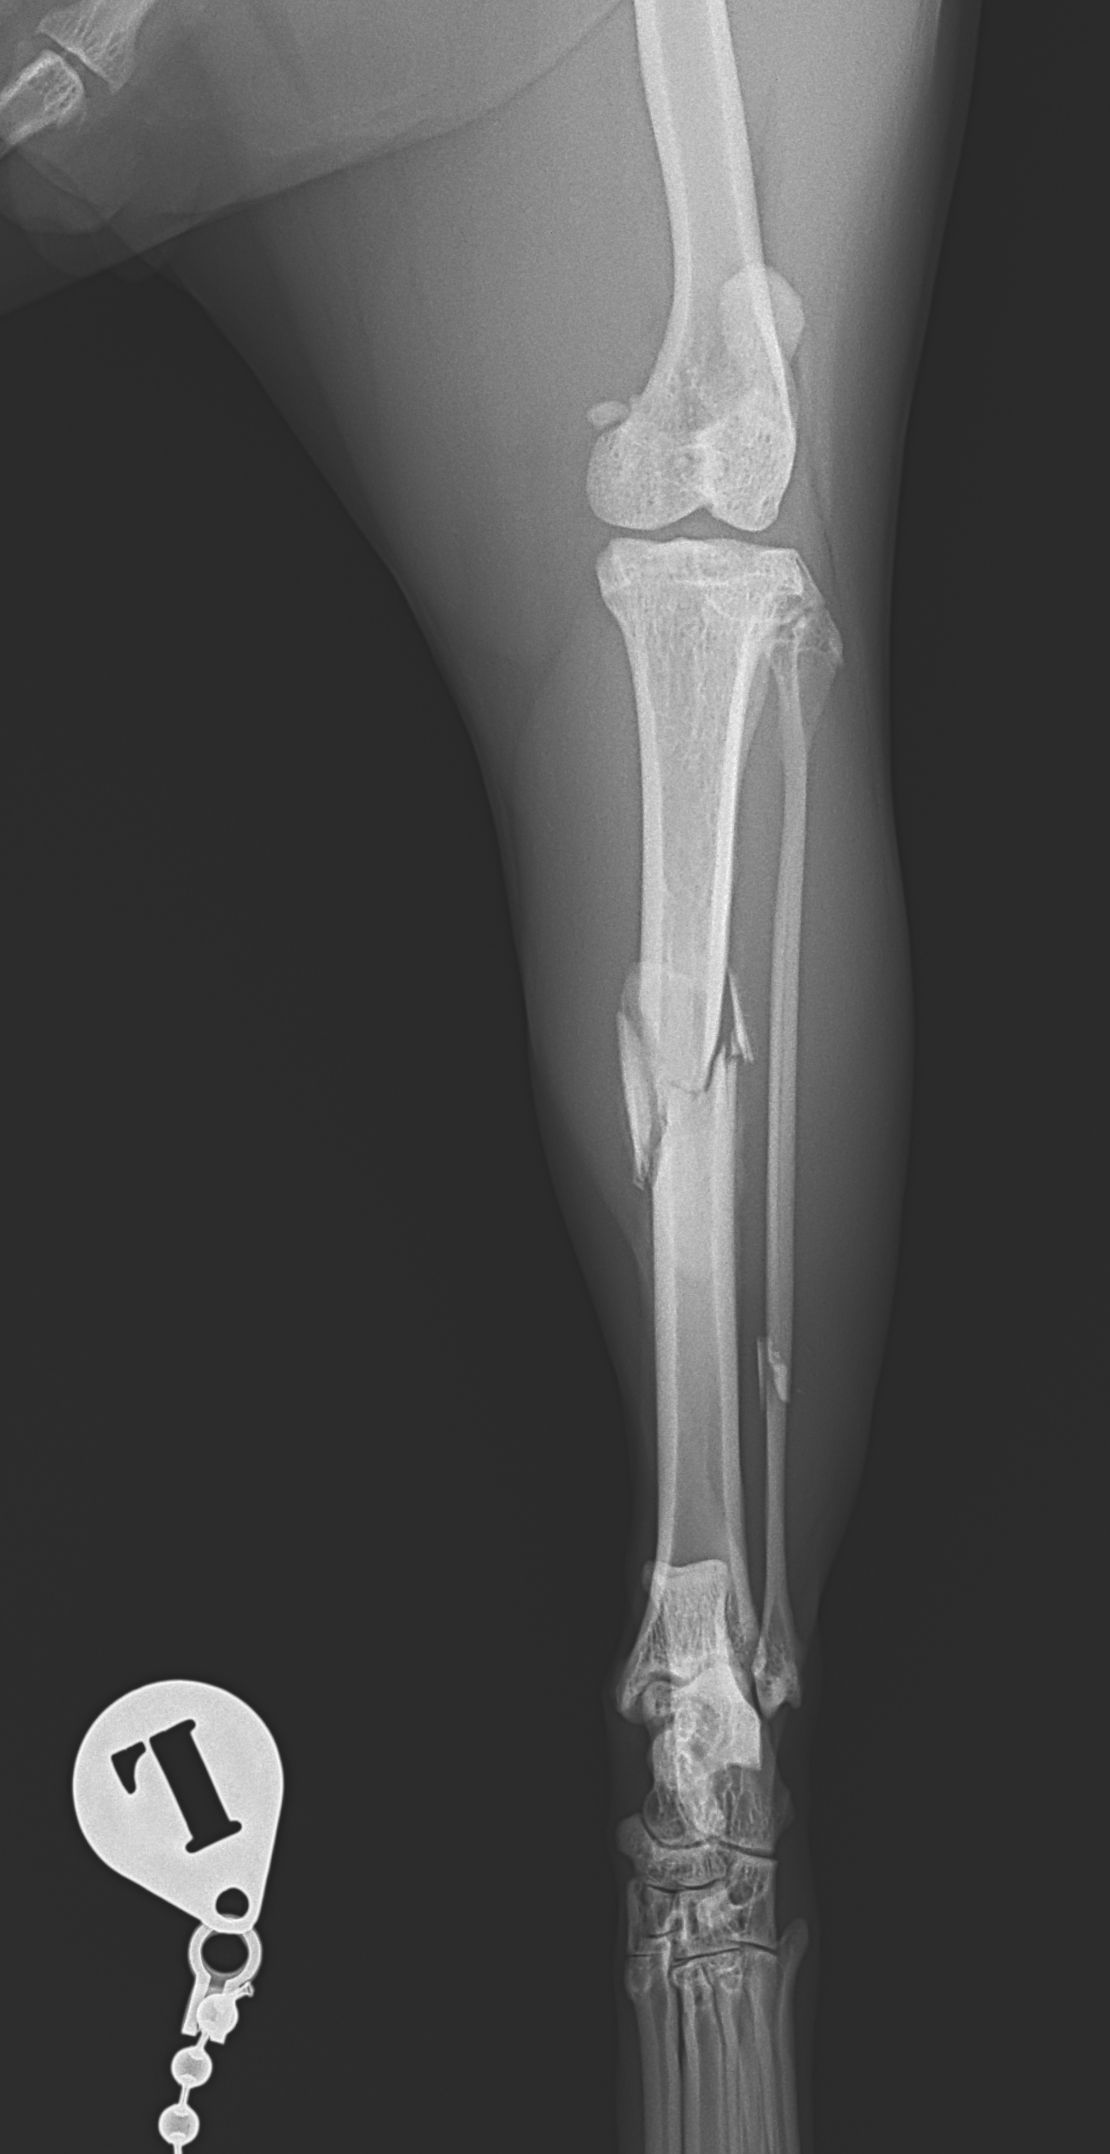

脛骨粉砕骨折に対するMinimally Invasive Plate Osteosynthesis

大型の猫に発生した脛骨(すねの骨)骨幹中央部の粉砕骨折 に対してIMピン併用でMIPO法(Minimally Invasive Plate Osteosynthesis) による整復固定術を行いました。

これらが極めて重要になります。本症例ではIMピンで軸方向の支持性を確保し、プレートで回旋・剪断力を制御することで、骨折部をほとんど展開せずに安定性を確保しました。

MIPO法は骨折周囲の軟部組織を温存できる一方で、正確なアライメント管理と固定設計が求められる手技です。術後X線ではアライメントは良好で、固定バランスも安定しています。今後は仮骨形成と骨癒合の経過を慎重にフォローしていきます。